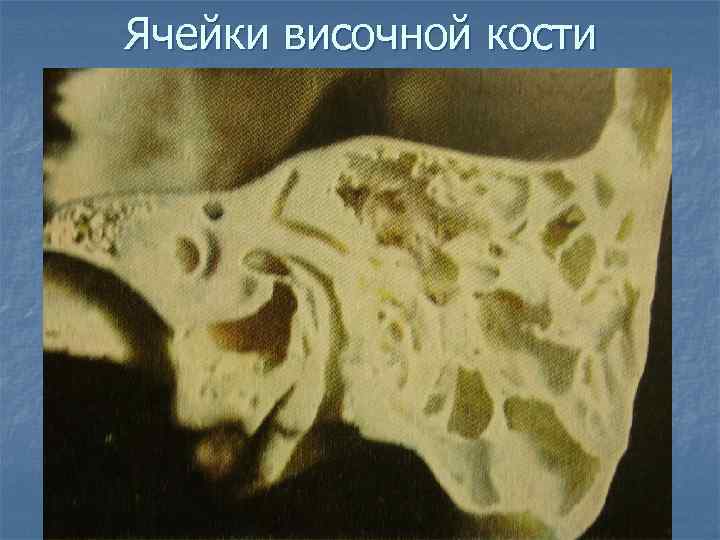

Анатомия сосцевидного отростка